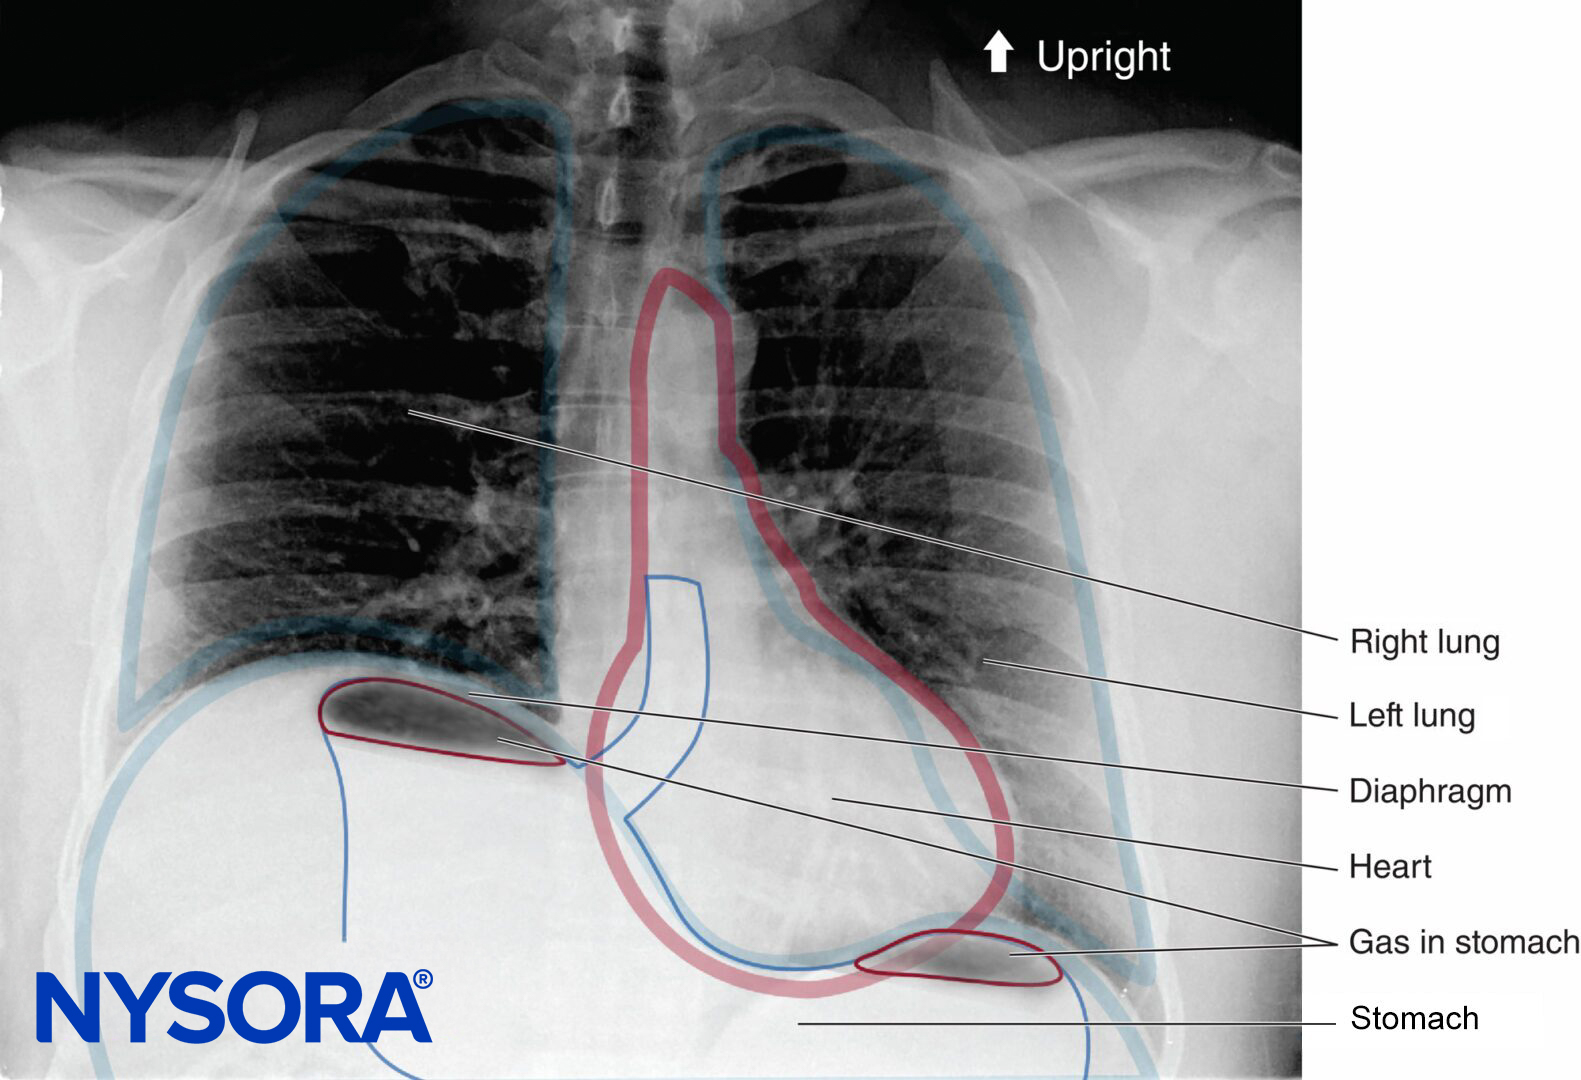

In the absence of rare complications such as pneumothorax, any alterations in respiratory mechanics seen with brachial plexus block are due primarily to phrenic nerve block and hemidiaphragmatic paralysis (Figure 1). This has been shown to occur in 100% of patients receiving interscalene block when performed without ultrasound guidance and using between 34 and 52 mL of local anesthetic. When diaphragmatic paresis occurs, there is an associated 27% reduction in both FVC and FEV1. While the clinical significance of this reduction in healthy patients is not entirely clear, it may be useful to risk-stratify patients about to undergo interscalene blocks as one would a patient undergoing lung resection. In other words, ask the question, “Will this patient tolerate a periopera-tive FEV1 reduction of 27%?”

FIGURE 48-1. Upright chest radiograph of a patient who underwent a right interscalene brachial plexus block. Note the elevated right hemidiaphragm.